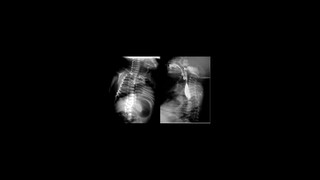

Características históricas de la radiología forence

Radiología forense